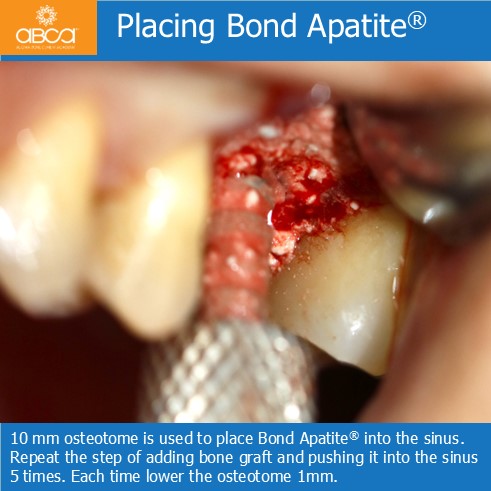

The patient is a 50 year old female with severe posterior maxillary atrophy. She came in for a posterior maxillary implant procedure. Implants were placed using Augma Lift™ Kit B.

Sinus lift with Augma Lift™ Kit B with 4-5 mm sub sinus bone height.

Sinus lift with Augma Lift™ Kit B when there is 6 mm Sub Sinus Bone Height

Sinus lift with Augma Lift™ Kit B when there is 6-7 mm Sub Sinus Bone Height.

Sinus lift with Augma Lift™ Kit B with 4-5 mm sub sinus bone height. A young woman came to replace the missing first maxillary molar with moderate atrophy.

Sinus lift with Augma Lift™ Kit B in a case with 5 mm sub sinus bone height.

Sinus lift with Augma Lift™ Kit B in a case with 5 mm sub sinus bone height. The patient came for implant treatment in the region of teeth #16 (3)…

Sinus lift with Augma Lift™ Kit B in a case with missing teeth #14 (5), #15 (4), #16 (3), #17 (2) and a sub sinus bone height of 6 mm.

Sinus lift with Augma Lift™ Kit B in a case with 6 mm sub sinus bone height.